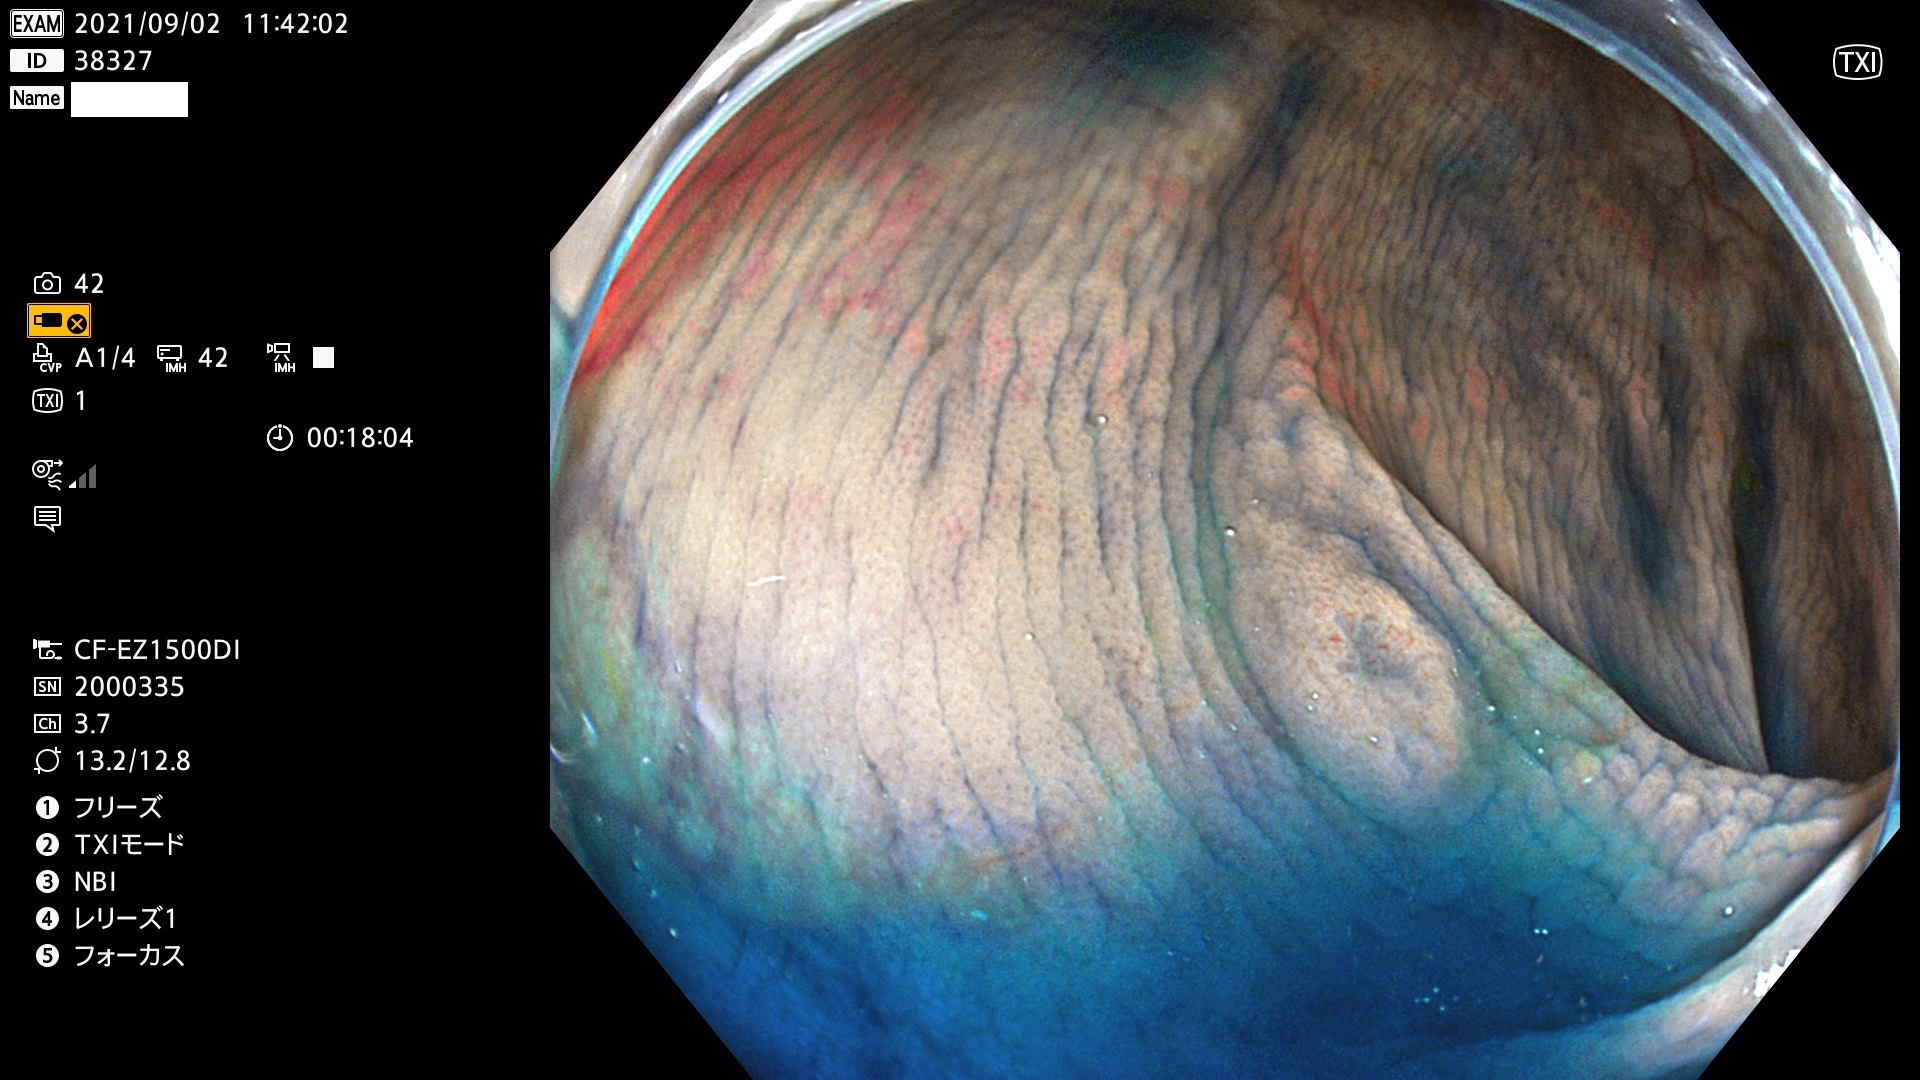

38300 38301 38302 38303 38304 38306 38307 38308 38309 38310 38311 38312 38313 38314 38315 38316 38317 38319 38321 38322 38323 38324 38325 38327 38331 38332 38333 38334 38337 38338 38339 38340 38341 38343 38346 38348 38349 38350 38351 38352 38353 38354 38355 38358 38359 38360 38361 38362 38363 38365 38366(SSAP) 38368 38369 38370 38371(SSAP) 38372 38374 38375 38376 38377 38378 38380 38381 38382 38383 38384 38385 38386 38388 38389 38391(SSAP) 38395 38397 38399

発見困難で危険性の高い平坦型病変(上記100名より抽出)